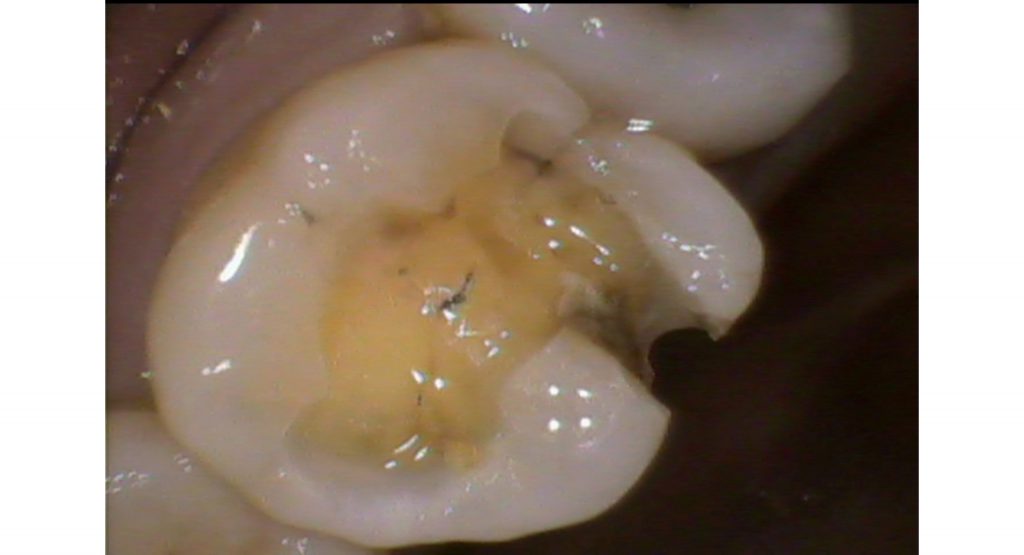

「磨き残しにより治療した歯に虫歯が再発した症例」

今回の症例は、左上6番目の歯の治療をしました

左上6番目の歯にはコンポジットレジンという保険治療でおこなう虫歯治療がされていました

治療したにも関わらず、虫歯ができていました

黒いところが歯が溶けている虫歯です

コンポジットレジンという保険治療の材料を除去すると

詰め物の中で虫歯で溶けていました

虫歯になっていても本人は自覚症状はありませんでした

そのせいで、虫歯が神経の近くまで進行している箇所もありました